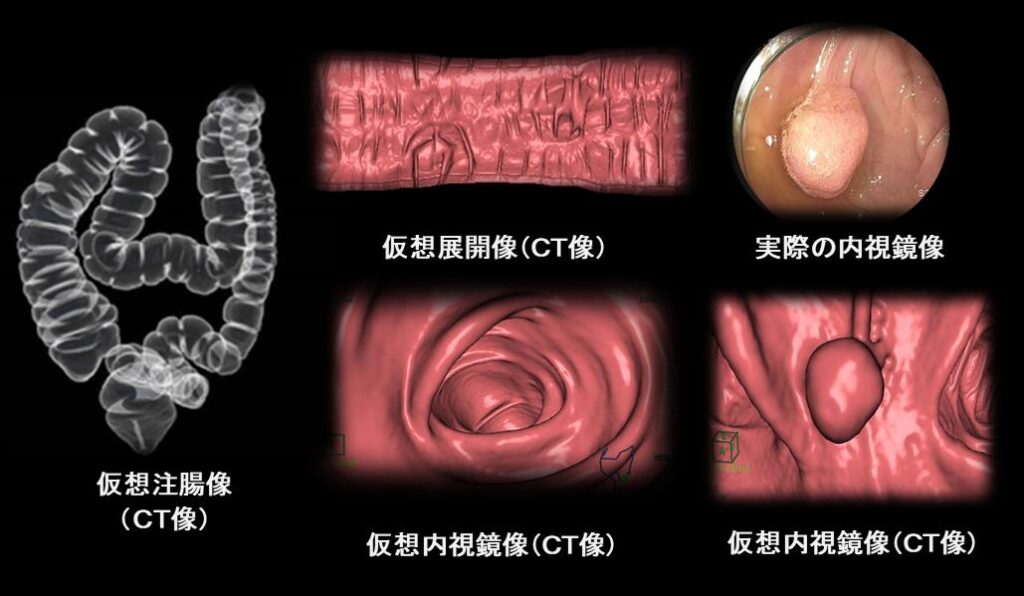

大腸CT検査について

- 内視鏡を使わない新しい検査です

- マルチスライスCT装置により3次元画像を作成して正確な検査が行えます

- 内視鏡挿入や造影剤注入の必要がないため苦痛の少ない検査です(吸収・排出されやすい炭酸ガスの注入は必要となります)

内視鏡検査

当院のマルチスライスCT装置では、鮮明で高精度な画像を撮影でき、さらに3D画像によって大腸内部を立体的に観察することが可能です。

これにより、見落としの少ないより正確な評価につながります。